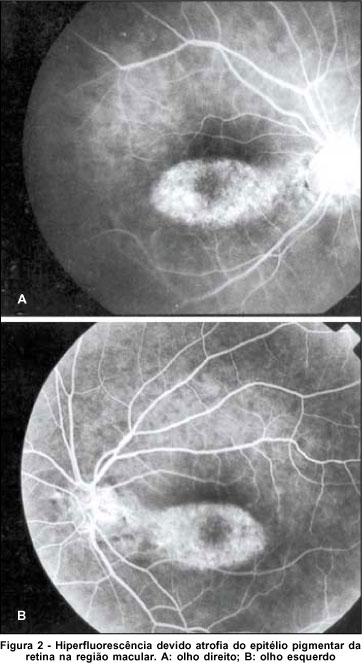

Paciente de 53 anos, sexo feminino, portadora de artrite reumatóide, fez uso de cloroquina por 6 anos e havia parado há um ano, quando veio ao nosso serviço. Apresentava acuidade visual em olho direito de 20/200 e em olho esquerdo de 20/40 sem melhora com refração. À biomicroscopia do segmento anterior apresentava lente intra-ocular no olho direito e catarata nuclear 1+/4+ no olho esquerdo, com córnea verticilata em ambos os olhos. À oftalmoscopia apresentava mácula com aspecto de tacho batido bilateral (atrofia do epitélio pigmentar da retina) (Figura 1). A angiofluoresceinografia mostrou uma área central hiperfluorescente resultado de defeito em janela do epitélio pigmentar da retina em ambos os olhos (Figura 2).